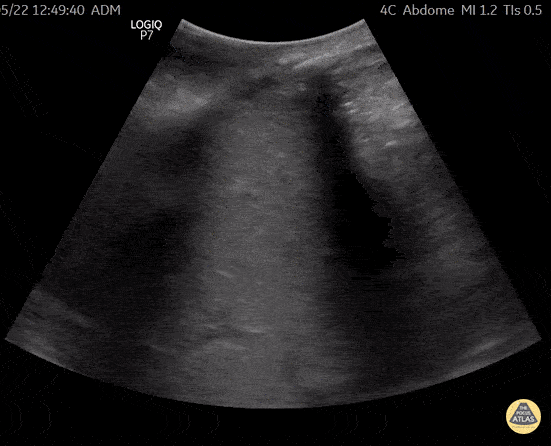

woman 64 a, brought to emergency due to abdominal pain, vomiting and nausea, abdominal pocus showed a large unilateral right hydronephrosis. The obstructive primary cause was a pelvic mass still under oncologic investigation. This is a right upper quadrant view, where a grade IV hydronephrosis is observed. This case demonstrates the importance of bedside ultrasound in the differential diagnosis of renal failure in the emergency room. @R_Tambelli